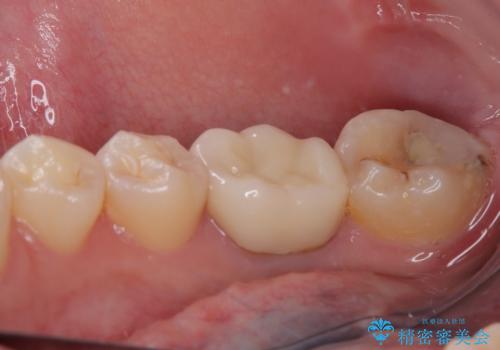

- 奥歯の歯肉から定期的に膿が出てくるとのことで来院された患者様です。

レントゲン写真などの診察を行った結果、根管治療が必要であったため、現在のクラウンを除去し、根管治療を行うこととしました。

根管治療後は症状を確認し、速やかにオールセラミッククラウンにて補綴治療を行うこととしました。